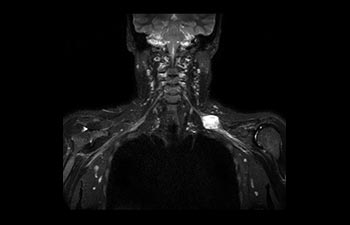

La Sra. Silvia Schiffer, directora y radióloga experta en la clínica Radiologie Schiffer, en Alemania, comparte sus experiencias con el sistema de RM Prodiva 1.5T.

Conozca la opinión de los primeros usuarios de Ingenia Prodiva 1.5T acerca de sus experiencias con el sistema y cómo influye este en su centro de diagnóstico por imagen.